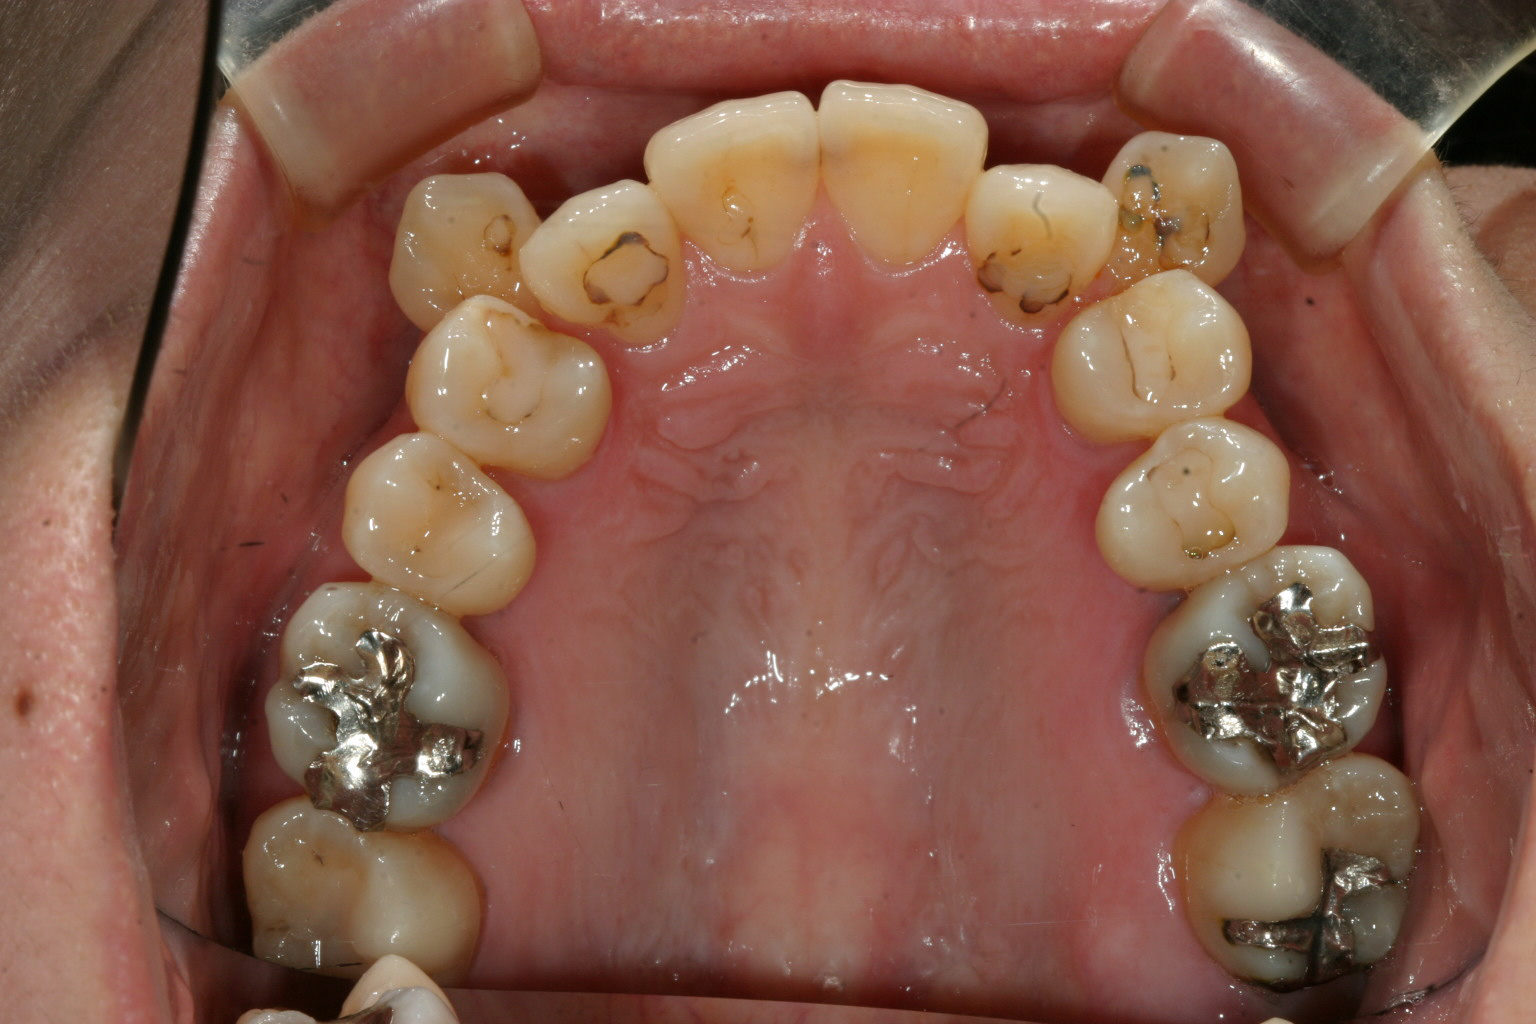

完全に犬歯が飛び出してます。こういう場合は後ろ隣の小臼歯抜いて出来たスペースに糸切り歯を入れます。

左側第二小臼歯が内転してますからこれを抜くことにしましょう。 右側の第二小臼歯も少し内転してますからこれも抜歯する事で左右のバランスを取ります。

犬歯の問題だけでオーバージェット(前歯の前突)はさほど見られません。